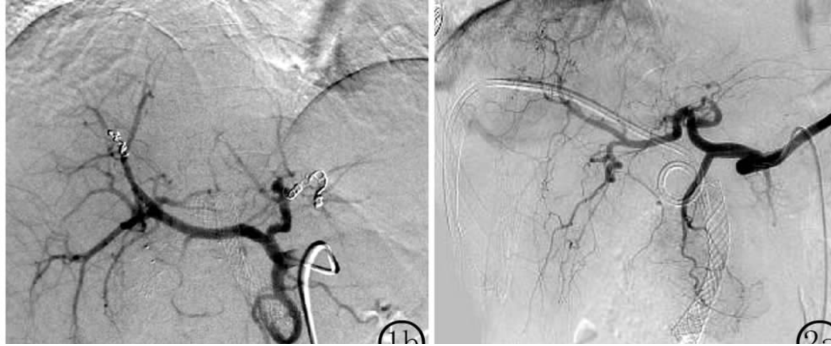

图:胆囊结石、胆总管结石术后 1 个月呕血及黑便;血管造影肝右动脉假性动脉瘤

图:胰十二指肠切除术后11天出现便血和黑便;肠系膜上动脉造影见分支动脉假性动脉瘤。